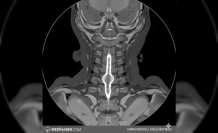

Omurga Sağlığında Sinsi Tehlike: Ankilozan Spondilit

Türkiye genelinde özellikle genç yetişkin nüfusu etkileyen ve halk arasında omurga iltihabı olarak bilinen Ankilozan Spondilit (AS) vakalarında artış gözleniyor. Uzmanlar bel ağrısı şikayetiyle başvuran hastaların büyük kısmında teşhisin geciktiğini belirtiyor. Genç yaşlarda başlayan ve hareket kısıtlılığına yol açan bu durum hastaların yaşam kalitesini doğrudan etkileyen bir faktör olarak karşımıza çıkıyor. Genellikle 20'li yaşların başında görülen belirtiler, sıradan bir bel fıtığıyla karıştırılabiliyor.